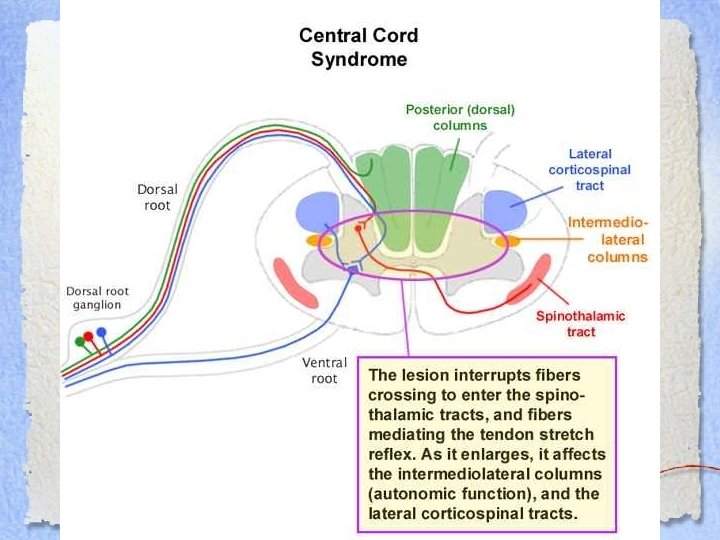

Central Cord Syndrome • Older patients • Preexisting central spondylosis • Hyperextension injury • Injury affects central cord> peripheral cord • Damage to corticospinal and spinothalamic tracts • Upper extremities>thoracic >lower extremities>sacral

Central Cord Syndrome • Older patients • Preexisting central spondylosis • Hyperextension injury • Injury affects central cord> peripheral cord • Damage to corticospinal and spinothalamic tracts • Upper extremities>thoracic >lower extremities>sacral

CCS • Present with: – Decreased strength – Decreased pain and temperature sensation – Upper>lower extremities – Spastic paraparesis/quadriparesis – Maintain bladder and bowel control • Prognosis: GOOD – Although fine motor recovery of the upper extremities is rare

CCS • Present with: – Decreased strength – Decreased pain and temperature sensation – Upper>lower extremities – Spastic paraparesis/quadriparesis – Maintain bladder and bowel control • Prognosis: GOOD – Although fine motor recovery of the upper extremities is rare